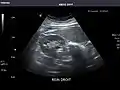

Right kidney

Kidneys: Right and left kidneys measure 11.5 cm and 12 cm in length respectively. No hydronephrosis. Small left lower pole kidney cyst.